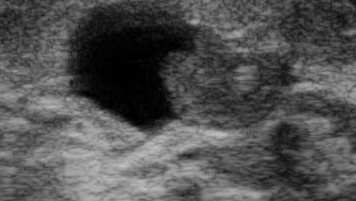

Внутрипротоковая папиллома молочной железы (УЗИ)